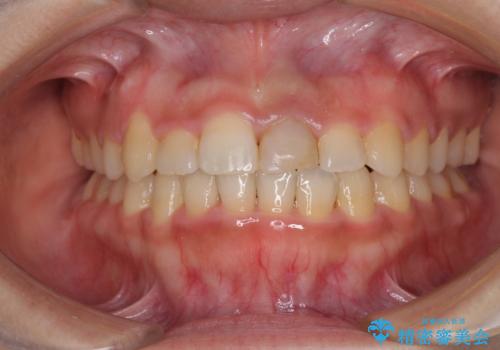

- 上顎前歯の隙間を気にして来院された患者様です。

目立たない装置を希望とのことで、インビザラインを用いて矯正治療を行うこととしました。

一度インビザラインのマウスピースセットをお渡しすると1年以上来院されず、マウスピースを破損したり紛失したりすると来院されるというのんびりとしたペースで治療を行ったため、4年間という長期にわたる治療となりました。

最終的には隙間は全て閉じ、綺麗な仕上がりとなりました。